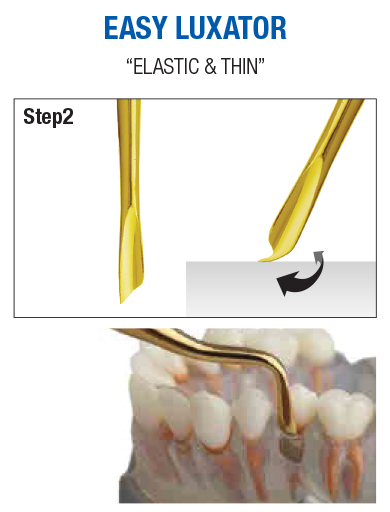

EASY LUXATOR is made of a special alloy, so it has elasticity and is thinner than other Luxators. It has the advantage of free from breakage, preserving the shape of the skeleton, and minimizing tissue damage.